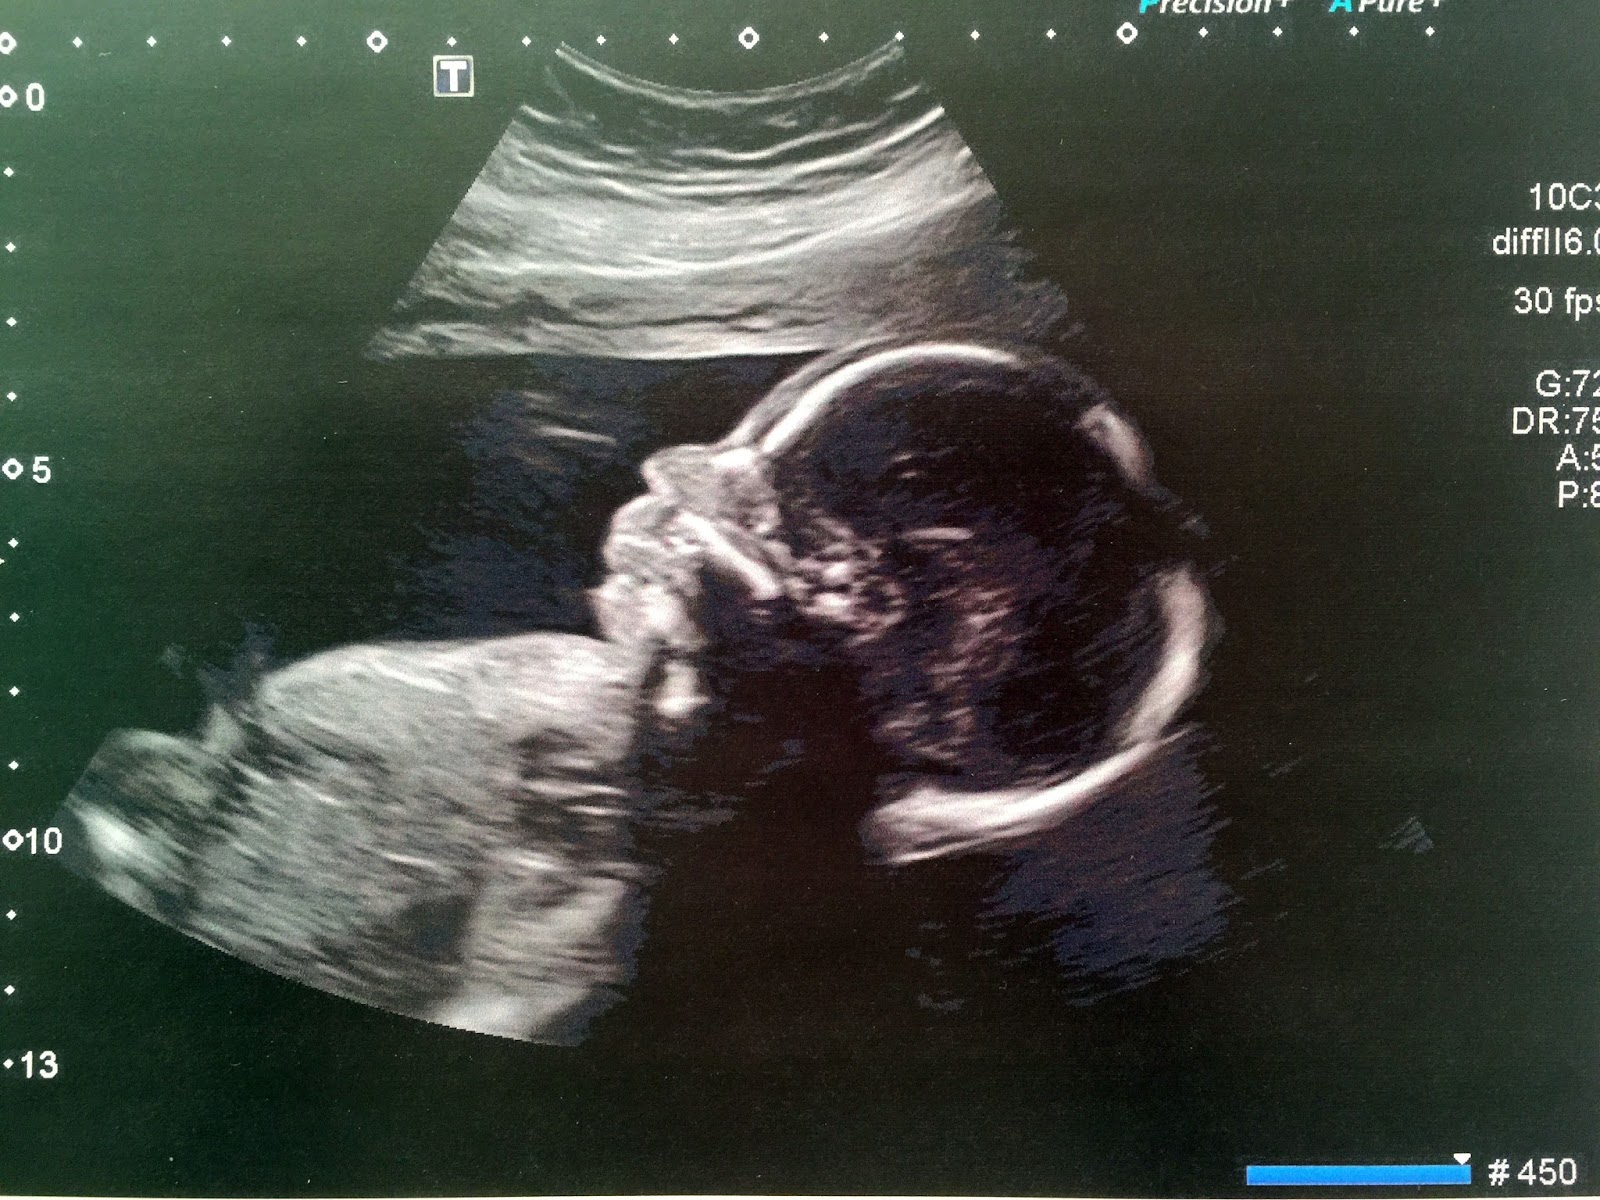

Elle a donc bien tout contrôlé et nous à rassuré en nous apprenant que tout allait très bien, que le développement et la croissance de bébé étaient parfaits, qu’il n’y avait à priori aucune malformation Un grand Ouf pour nous ! Non parceque malgré tout, on ne veut jamais penser au pire, mais il y a toujours une petite partie de nous qui se l’imagine…

Après les examens « médicaux », est venu le moment d’apprendre le sexe !

Quand elle à commencé à descendre, le suspense était à son comble pour mon mari et moi ! Puis, arrêt sur image, et là, il a fallu en déduire sans aucun doute possible que c’est…………… Un garçon !

La surprise était totale ! Je crois que j’ai dû être en état de choc pendant quelques secondes. Moi qui m’étais secrètement persuadé que j’attendais une petite fille, mon cerveau à eu du mal à l’admettre et je me suis entendu demander à la sage-femme : » C’est un garçon ? », malgré l’évidence…